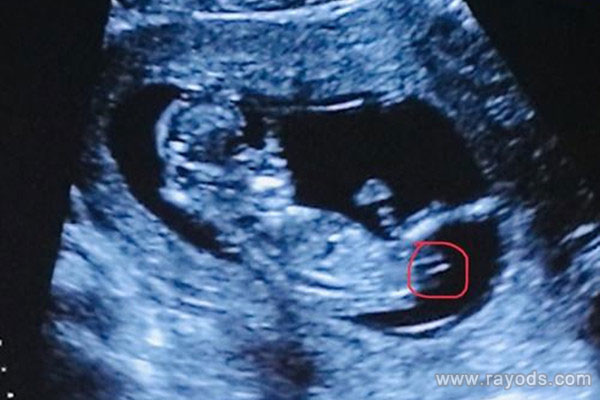

有经验的妈妈们说,nt检查可以看图像显示,若是生殖器部位有小突起;特征点与躯体成大于30度角;B超图像上没有三条白线,那么怀孕男孩的可能性就非常大。

怀男孩和怀女孩,B超图像上是不一样的,我们可以从宝宝下半身特征点来做区分。但事实上,医生做nt检查时,一般会避开胎儿的下半身,所以无从知晓男女。